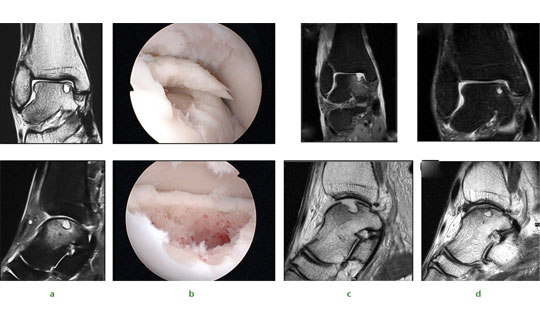

Stem cell therapy is not just applicable to the knee, however, and we have successfully applied this technique to a range of joints. The ankle shown in Figure 3a exhibits a typical appearance of a large post-traumatic chondral injury sustained by a 36-year-old male while snowboarding. Pre-operative MRI scans and arthroscopic findings were consistent with a medial talar dome chondral lesion. A similar operative approach is used with debridement and subchondral drilling approach is used comprising of debridement (Fig.3b) followed by stem cell therapy. The patient’s subsequent postoperative (Fig.3c) and nine-month MRI scan remarkably show almost complete healing of the chondral lesions (Fig.3d).

Fig. 3 Images of a 36-yearold man who sustained chondral injury.

Figure 3a – ankle joint showing medial talar dome chondral lesion with underlying subchondral cyst.

Figure 3b – views following subchondral drilling around the lesion and into the cyst.

Figure 3c – post-operative MRI scan following subchondral drilling (Sagittal PD and Coronal PDFS).

Figure 3d – MRI scans at nine months showing healing of the chondral lesion.